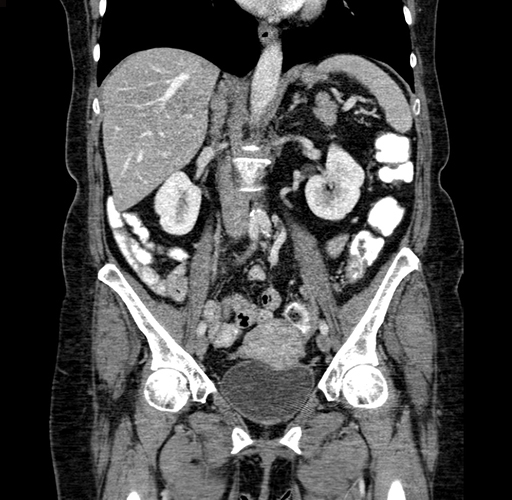

Pre-Chemo: Coronal Venous